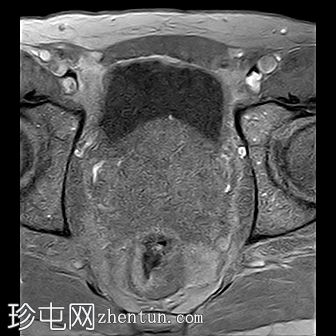

轴位

T2加权像

前列腺增大,大小为52 x 56 x 57 mm(体积87 ml)。

PSA 7.279 ng/ml,PSA密度0.084 ng/ml/cc。

在前列腺中部/尖部,右侧外周带/周围膜交界处可见一大小为7 x 5 mm的毛刺状、边界不清的T2低信号病灶,伴有扩散受限和早期动脉期强化,提示为PI-RADS 4级病灶。

边界清晰的T2高信号结节,典型良性增生,在移行区(TZ)最大直径达18 mm,符合PI-RADS 1级。

左侧精囊皱襞基底部类似良性左侧前区a(PZa)结节。

基底部向膀胱内突出。